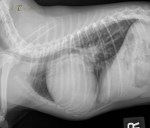

Latérale gauche